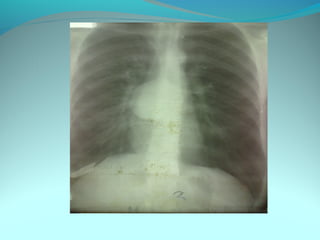

cliché de mauvaise qualité

Clarté retroclaviculaire gauche d 3cm de diam

entouré d’une paroi de 1cm d’epaisseur

La limite interne se confend avec le mediastin

Les autre limites sont nette

DIAGNOSTIC

Caverne tuberculeuse gauche